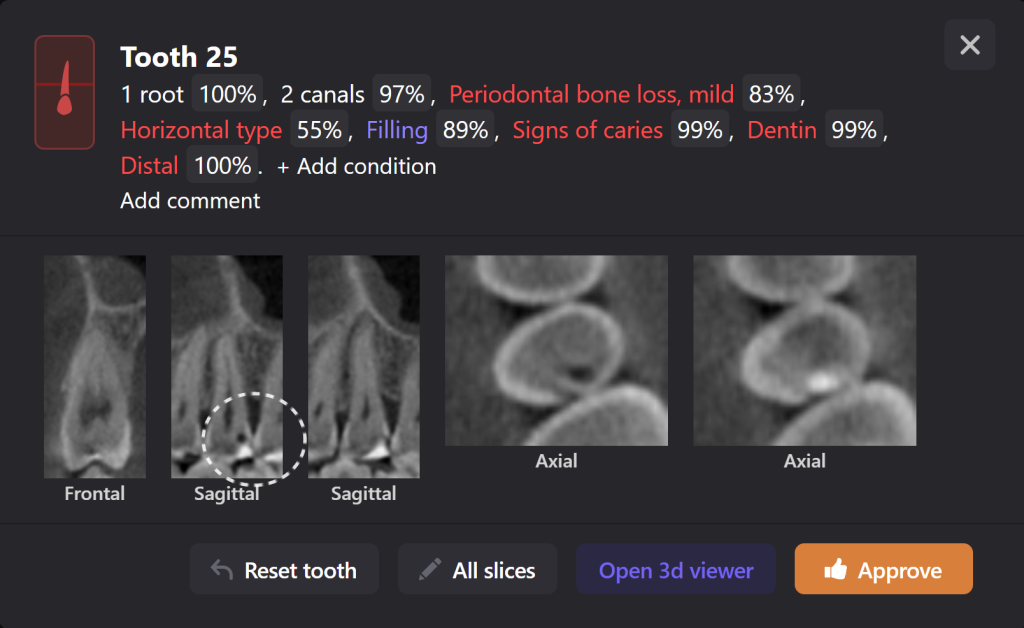

Diagnocat determined not only the presence, but also the localization of the focus of radiolucency of enamel and dentin, which was correctly indicated as “signs of caries” in the report

During a clinical examination, it is difficult to verify the presence of caries located under a filling, which is why the information obtained during a radiological examination is so important

Please note that despite the fact that the radiolucent area is poorly visible when viewing CBCT, Diagnocat reflected in the report the presence of signs of caries and accurately indicated the localization